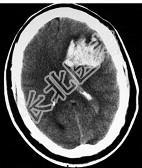

- 单项选择题男,52岁, 既往检查有脑动静脉畸形,突发站立不稳伴恶心呕吐4小时, 请结合影像图像选择最可能的诊断 ( )

A、脑出血

B、脑脓肿

C、脑转移瘤

D、脑梗死

E、颅内动脉瘤